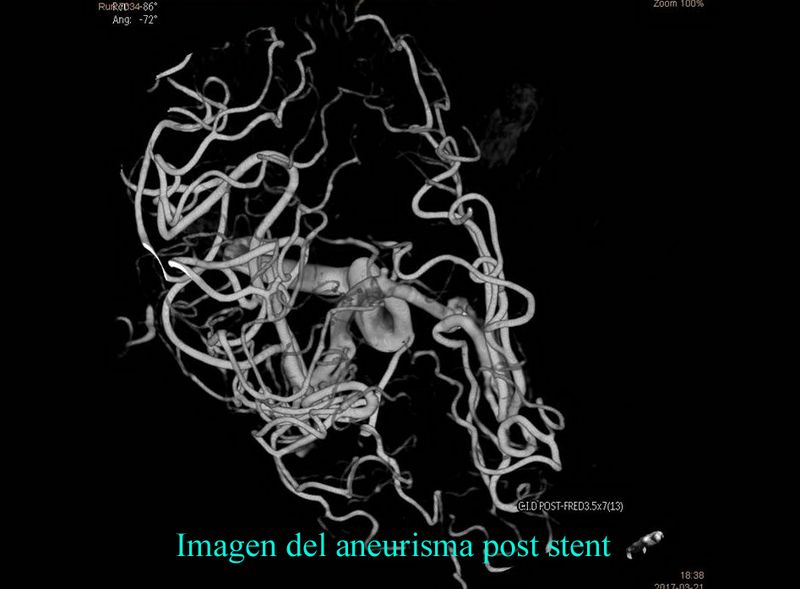

Aneurisma de cara posterior de A1